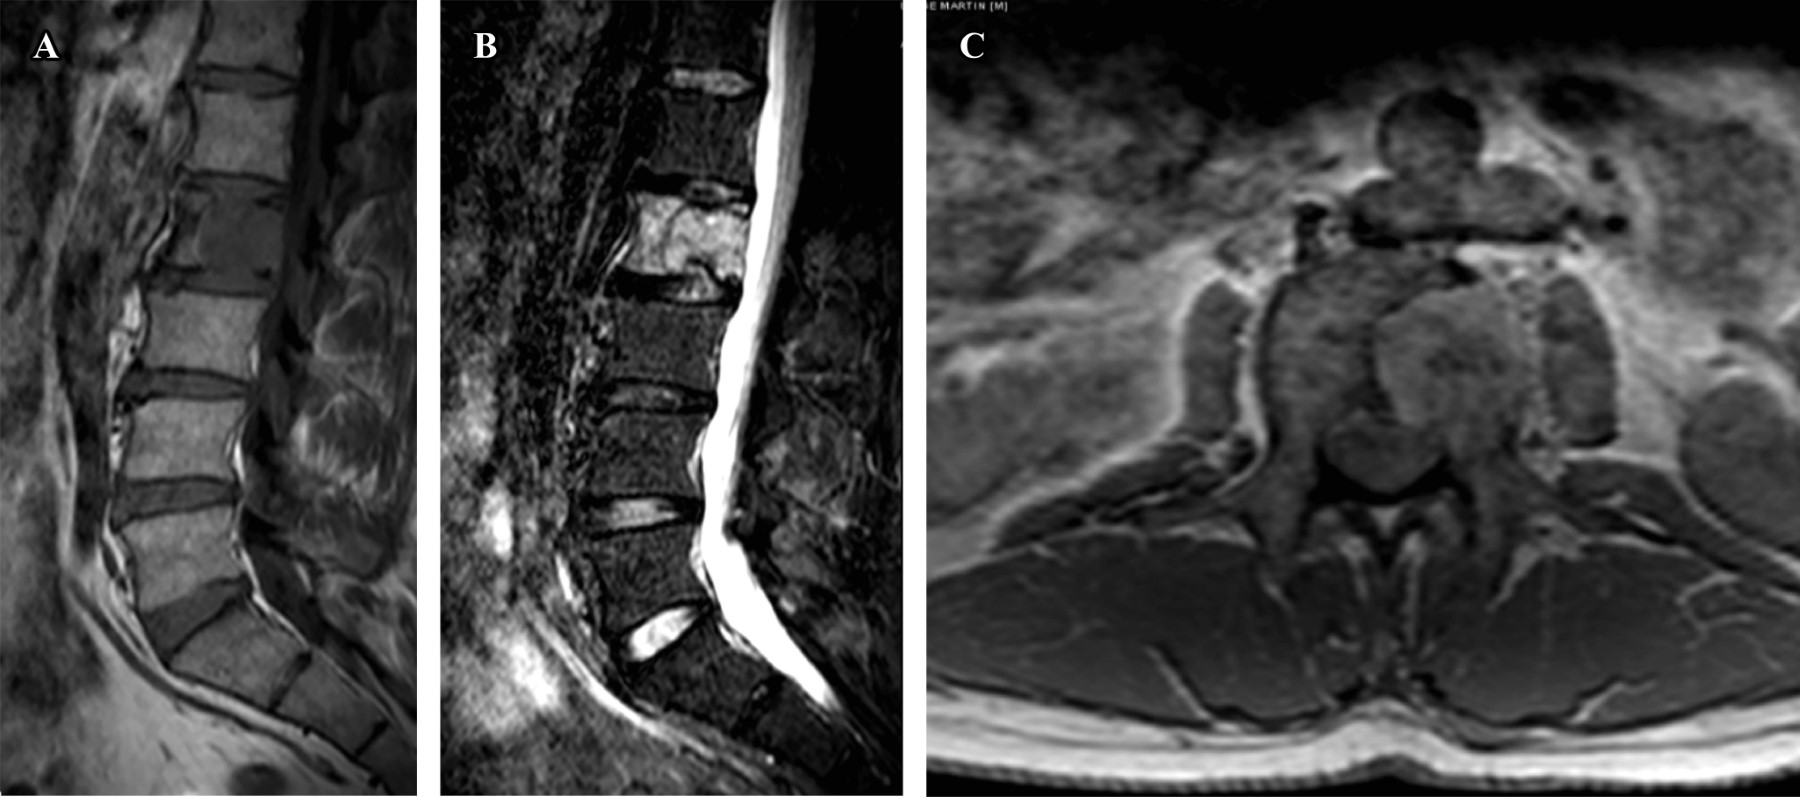

El paciente aporta una tomografía axial computarizada (TAC) y una resonancia magnética nuclear (RMN) (Figuras 1 y 2) que muestran una lesión lítica inespecífica en la espinosa de T1 y otra lesión en el cuerpo vertebral de L2. Ante estos hallazgos, se solicita una gammagrafía y una TAC toracoabdominal y se reprograma al paciente en una semana en consultas. Se realiza la gammagrafía que sólo muestra captación a nivel de ambas lesiones vertebrales. La TAC toracoabdominal informa de un enfisema paraseptal con atelectasias en el lóbulo inferior derecho y un área inespecífica en vidrio deslustrado en el lóbulo medio, sin alteraciones en el parénquima pulmonar ni otras lesiones a nivel abdominal.

Figura 2